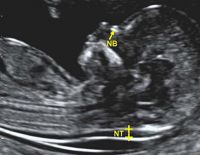

Độ mờ da gáy bình thường là bao nhiêu, tại sao phải đo?

Độ mờ da gáy bình thường là bao nhiêu, tại sao bác sĩ phải đo độ mờ da gáy là những kiến thức cơ bản bạn phải nắm vững. Đây là một thông số quan trọng giúp bác sĩ xác định xem bé có khỏe...